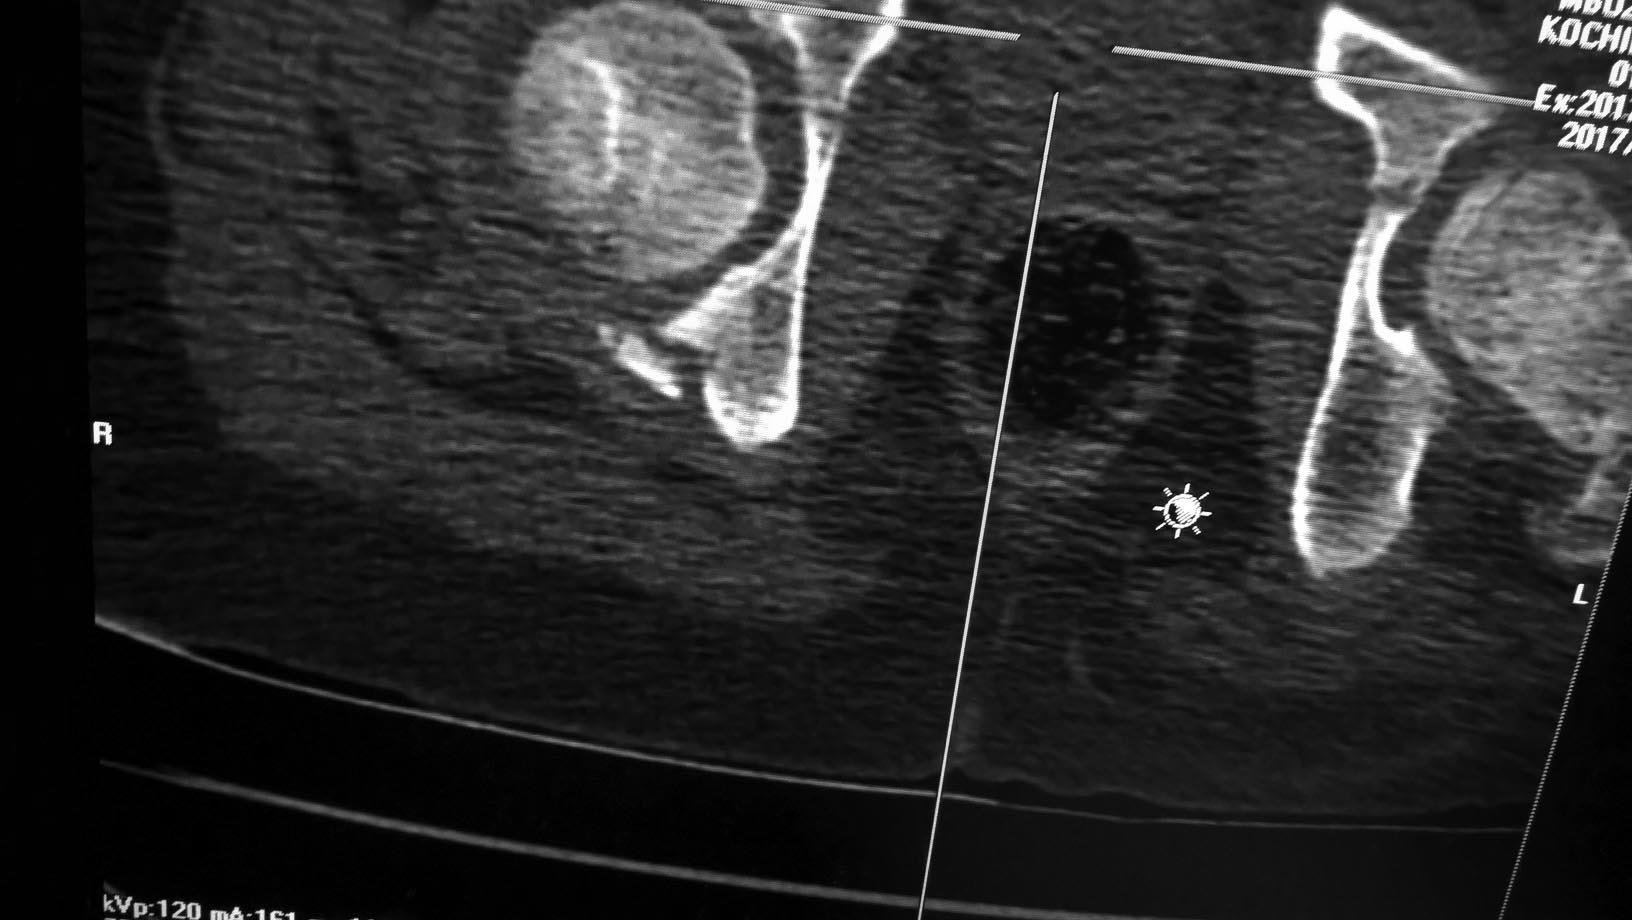

Перелом вертлужной впадины у ребенка

Добры день, коллеги! Помогите пожалуйста определиться с тактикой ведения больного. Ребенок 11 лет (мальчик), травма 04.07.17г: падение с высоты 3м.

Вот такой вот перелом вертлужной впадины. Есть ли необходимость в фиксации перелома? Или будет достаточно 3 недели вытяжения, далее иммобилизация? Спасибо.

Консервативно,на скелетном вытяжении.